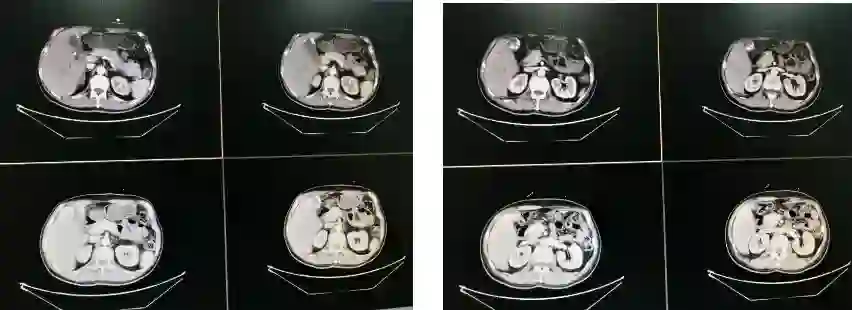

图1 术前腹部CT平扫图